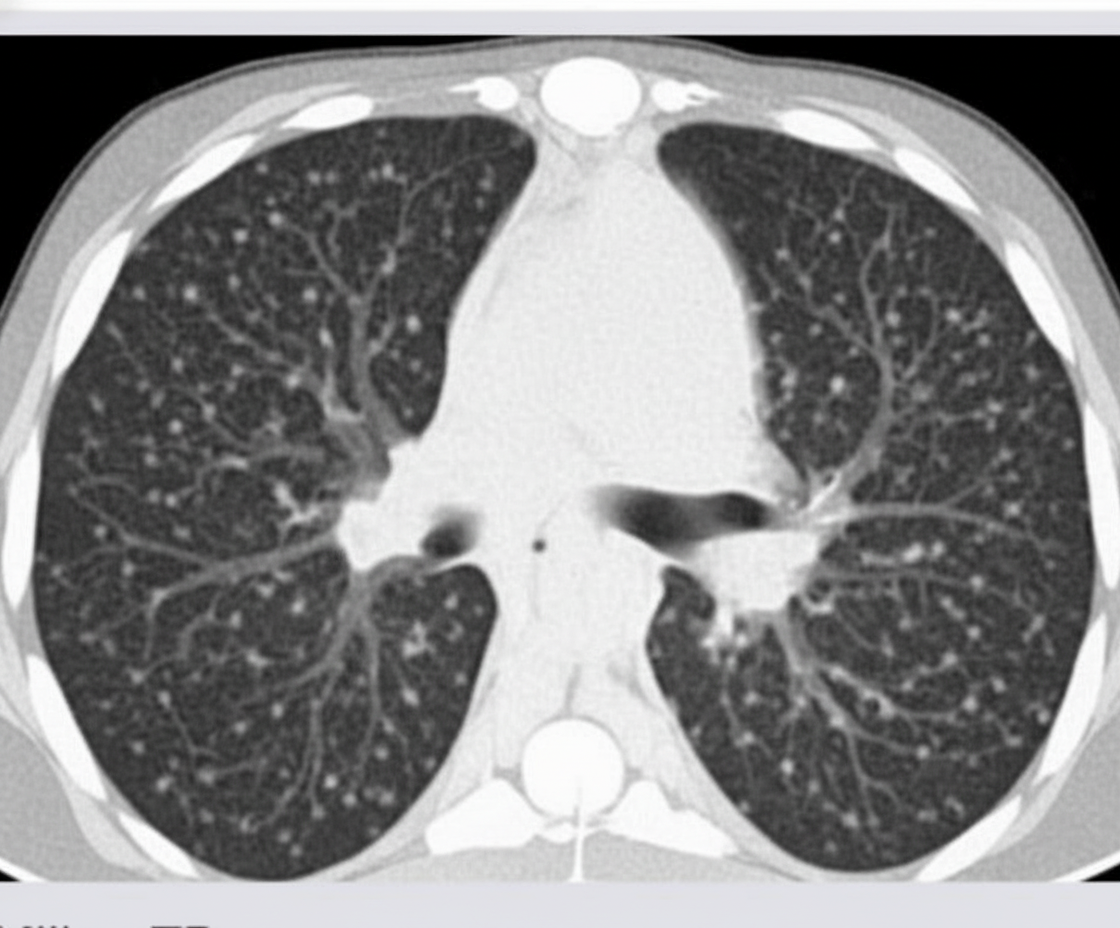

All are differential diagnoses for the CT chest finding shown, except?

Explanation: ***Diffuse pulmonary lymphangioleiomyomatosis*** - **LAM** characteristically presents with **diffuse thin-walled cysts** throughout both lungs, not a miliary/micronodular pattern. - This **cystic pattern** is pathognomonic for LAM and easily distinguishable from the nodular findings described in the CT. *Hemosiderosis* - Can present with **bilateral diffuse micronodules** due to **hemosiderin deposition** in pulmonary macrophages. - Often shows **ground-glass opacities** with micronodular pattern on high-resolution CT, fitting the described finding. *Tropical pulmonary eosinophilia* - Caused by **filarial infection** and presents with **bilateral diffuse micronodular** or reticulonodular opacities. - Associated with **peripheral eosinophilia** and **elevated IgE levels**, commonly showing miliary pattern on imaging. *Collagen vascular disorders* - Conditions like **systemic sclerosis** and **rheumatoid arthritis** can cause **diffuse micronodular** interstitial patterns. - Often progress to **honeycombing** and **fibrosis**, but early stages show fine nodular opacities matching the CT finding.